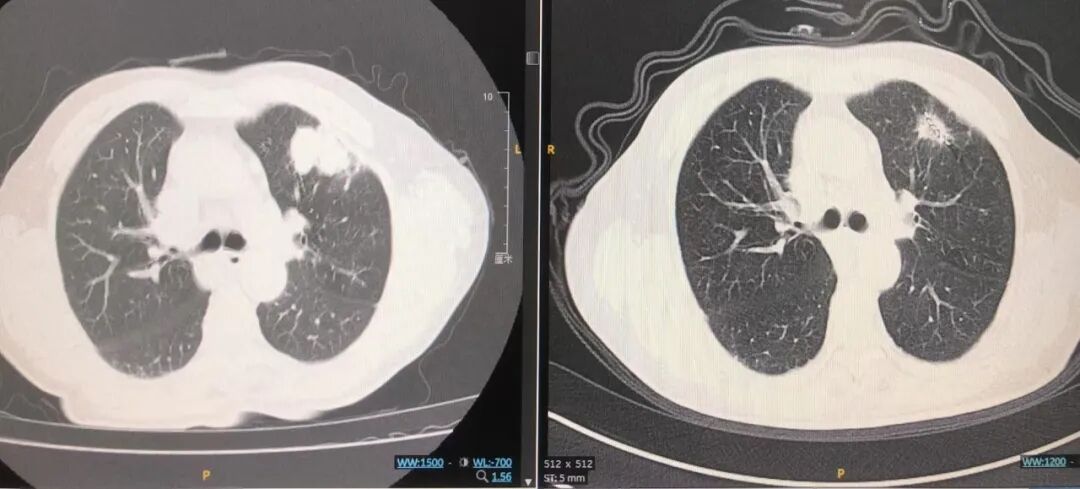

几乎与此同时,隔壁病房的周大爷(化名)也面临着类似的困境。他被初诊为左下肺鳞状细胞癌、慢性阻塞性肺病、Ⅱ型呼吸衰竭,肺功能极差无法进行外科手术。周大爷同样坚决拒绝了抗肿瘤放化疗及免疫治疗等传统方式,导致治疗一度陷入僵局。然而,在看到张大娘的病情得到显著改善后,周大爷主动要求尝试肺放射性粒子置入术。

王海英团队在排除相关手术禁忌后,同样成功为周大爷实施了碘125粒子植入治疗。手术过程非常顺利,术后周大爷的恢复情况同样令人满意。

图片VxG帝国网站管理系统

▲周大爷术前术后对比图VxG帝国网站管理系统

后续随访评估显示,张大娘和周大爷的病灶均有明显缩小,疗效显著。这一创新疗法不仅为患者带来了身体上的改善,更重要的是给予了他们后续治疗的信心与希望。